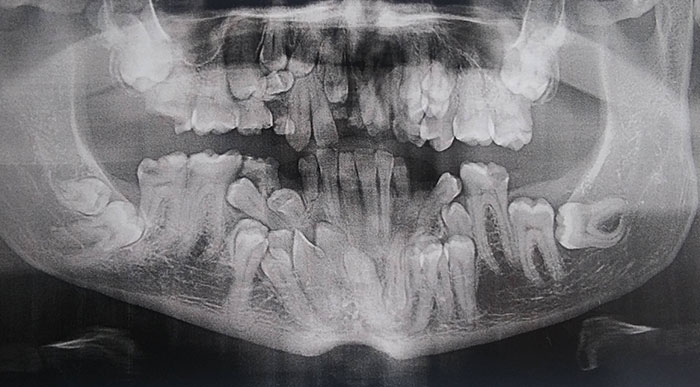

Стоматологические Исследования: Рентген Инвагинации Зубов